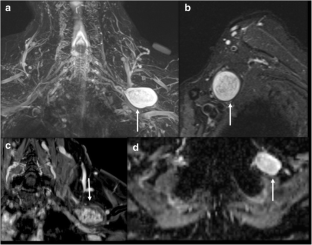

Fig. 2